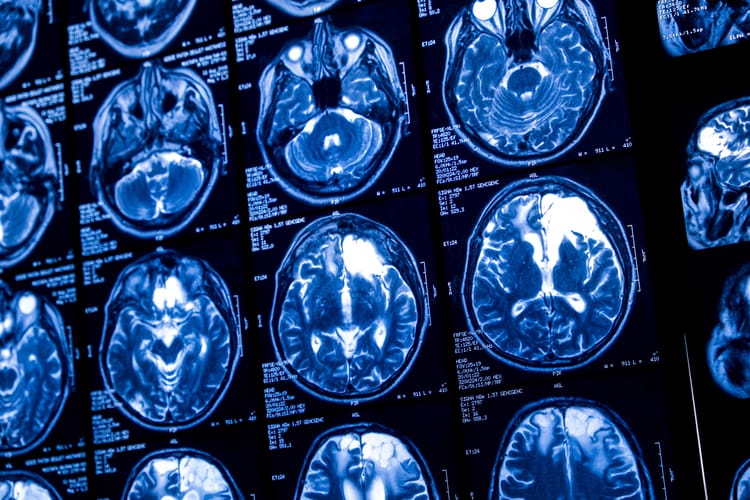

Najnowsze badanie Global Brain Health Institute w Trinity College w Dublinie wykazało wpływ czynników środowiskowych na wiek biologiczny mózgu. Przyspieszał lub się opóźniał z powodu zanieczyszczenia powietrza, warunków mieszkaniowych, opieki zdrowotnej czy równości społeczno-ekonomicznej.

Podsumowanie badania opublikowano w czasopiśmie „Nature Medicine”. Naukowcy wykorzystali pochodzące z 34 krajów dane dotyczące 18 701 osób – czynniki środowiskowe wpływały zarówno na mózgi osób zdrowych, jak i tych z chorobami neurodegeneracyjnymi.

Połączone czynniki fizyczne (zwiększone zanieczyszczenie, ekstremalne temperatury i brak terenów zielonych) były przede wszystkim związane ze strukturalnym starzeniem się mózgu, w szczególności w obszarach kluczowych dla pamięci, regulacji emocji i funkcji autonomicznych.

Z kolei czynniki społeczne (ubóstwo, nierówności, brak wsparcia) silnie wpływają na proces starzenia się mózgu i są powiązane z obszarami mózgu odpowiedzialnymi za myślenie, emocje i zachowania społeczne.

Badacze podejrzewają, że mózg stale adaptuje się do długotrwałego stresu, a połączone czynniki środowiskowe mogą mieć większy wpływ na starzenie się mózgu niż choroby takie jak demencja czy upośledzenie funkcji poznawczych.